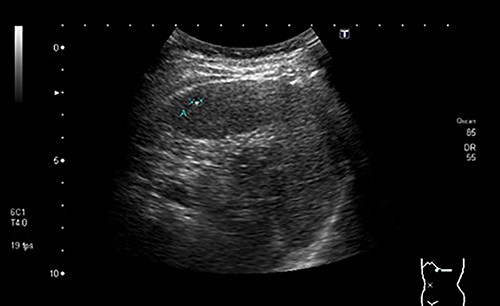

During a screening imaging examination of her liver disease, a lesion suspected of malignancy was detected. The ultrasound disclosed a hypoechoic nodule, vaguely heterogeneous, located in segment VII, subcapsular, and with ~22 mm in diameter (Fig. 1). Liver blood tests and serum alpha-fetoprotein level were normal. For better characterization, a CT scan was performed. The CT showed, in addition to signs of chronic liver disease, the presence of a solid subcapsular nodule of segment VII, measuring 23 mm, with hypervascular behavior in the arterial phase (Fig. 2) and washout in late venous phase (Fig. 3).

CT scan showing, in addition to signs of chronic liver disease, the presence of a solid subcapsular nodule of segment VII, measuring 23 mm, with hypervascular behavior in the arterial phase.